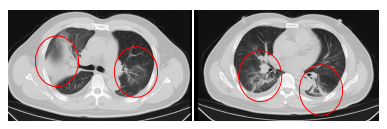

胸部CT成果骄气,他的双肺存在大面积的炎症病变,当场被转至感染科收受治愈。

过程治愈,顾先生的发烧、咳嗽、胸闷等症状逐步缓解,肺部炎症显著改善,现已康复出院。